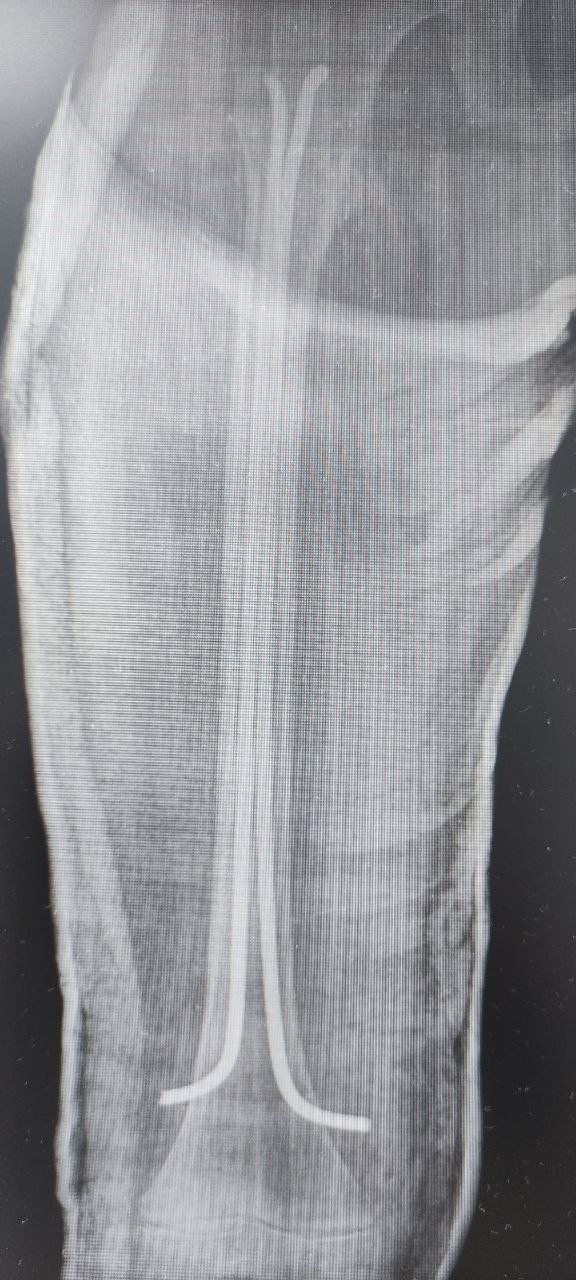

Инцидент произошел накануне. Мальчик попал в приемно-диагностическое отделение ДРКБ и был срочно прооперирован. Сейчас он находится в отделении травматологии и ортопедии, его состояние стабильное.

На сращение перелома уйдет 5–6 недель, а на реабилитацию — несколько месяцев, в зависимости от особенностей организма и соблюдения рекомендаций врачей.